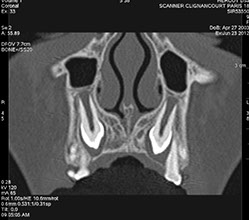

Le scanner dentaire se fait à l'aide d'un appareil équipé d'un tube à rayon X. Lors du déroulement de l’examen, le tube du scanner est en rotation autour du patient qui est placé sur un lit mobile. L'appareil permet alors de réaliser une imagerie en "coupes", utile à l'exploration des dents et des arcades dentaires. Grâce à un traitement informatique et à ces clichés, il est possible de reconstruire des images en 2D ou 3D (modélisation dans l’espace).

• Bilan avant pose d’implants dentaires, pour repérer les zones de passage des nerfs et mesurer l’épaisseur de l’os afin de calculer les dimensions optimums de l’implant.

• Bilan avant extraction dentaire (dents de sagesse) ou avant soins.